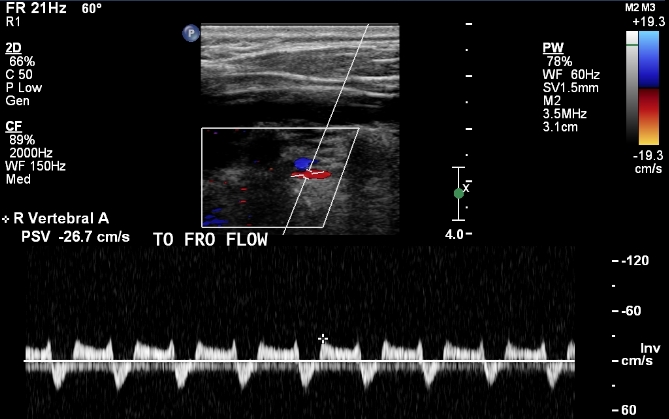

Some patients have “pre-steal”. If you scan them you will actually see normal, antegrade, flow in the vertebral artery. To produce the reverse flow you will need to increase flow in the arm. To see the reverse flow, the patient will need to use their arm. Another way is by inflating a blood pressure cuff and then deflating it. This causes reactive hyperemia. More blood flow goes to the arm and less to the brain. The following image shows the final stage of vertebral steal from severe right proximal subclavian artery stenosis:

subclavian steal syndrome vertebral flow pattern on ultrasound

Right retrograde vertebral artery flow on ultrasound